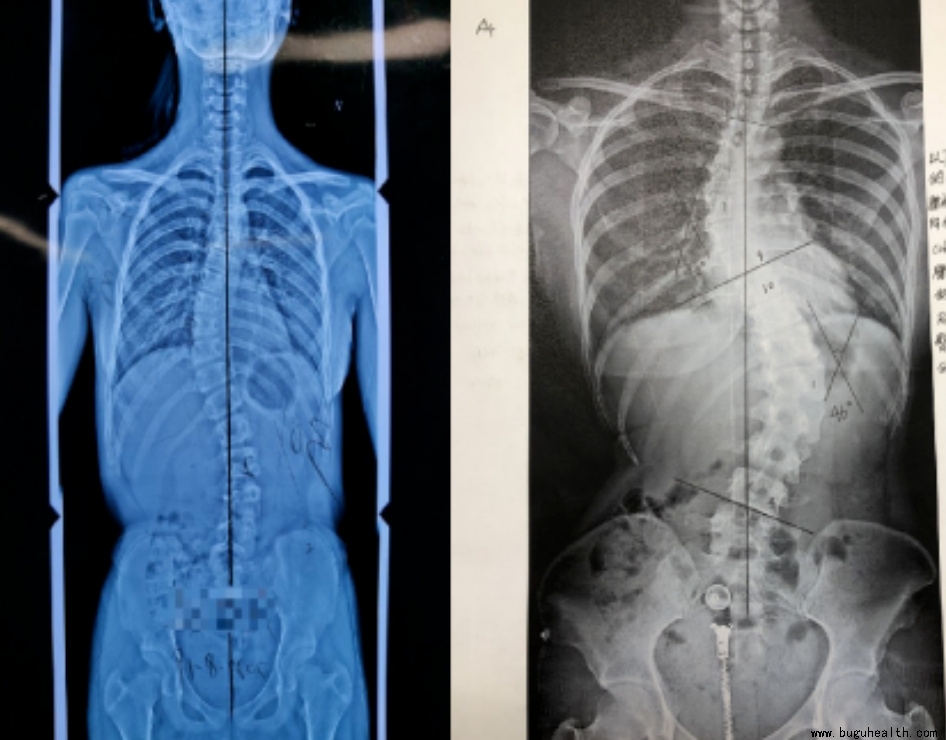

例子一:这是一个12岁的孩子,平时住校,当我们看到第一张图的时候好像没有什么问题,当脱去外套的时候,只是发现两边肩膀不一样高,好像也没有什么大问题,但是当她弯腰的时候就很明显看出脊柱两边的肌肉不一样高,就是剃刀背已经很明显了,最后我们再来看看拍出来的片子,孩子的侧弯已经很大了。那她是怎么发现的呢,孩子平时一点感觉都没有,全身不痒不痛,有一天洗澡的时候被同学发现背部两边差别很大,才让父母带来看,才发现是脊柱侧弯。

例子二:这是一个14岁的男孩,也是住校,父母常年在外务工,当父母过年回家发现孩子背部不对劲的时候,来检查侧弯已经很大很大了,孩子侧弯度数这么大也是不痒不痛,但是这个70多度的侧弯只能做手术了。

例子四:你以为侧弯只发生在十多岁的孩子身上吗,我们来看看一名6岁小朋友的侧弯,孩子妈妈一开始感觉孩子两边肩膀不一样高,以为是孩子坐姿不对,自己在家纠正一段时间后一点效果都没有,来医院检查才发现是脊柱侧弯。